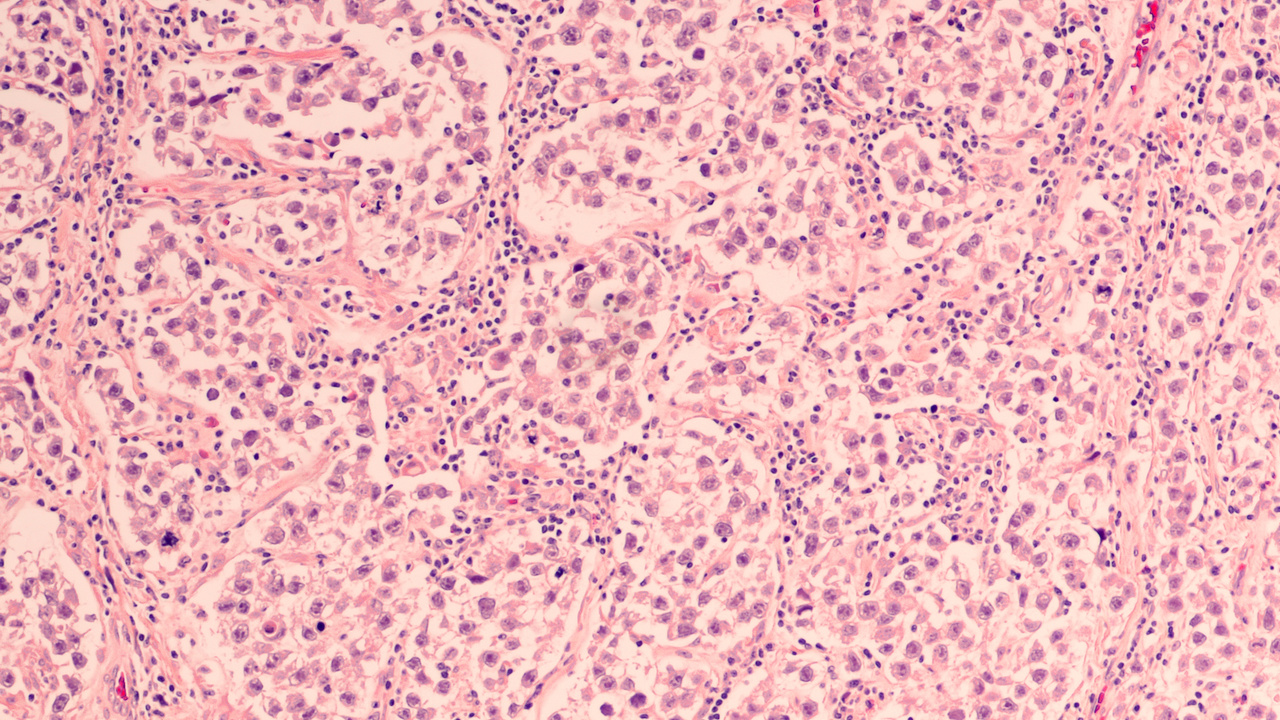

Testicular cancer, illustration and light micrograph Stock Photo Alamy Testicular Cancer Kind It's important to know the type of cell the cancer started in and what kind of cancer it is because they differ in how they're treated and in their. Many types of cells are found in. Which treatment options are best for you depends on. Testicular cancer treatment often involves surgery and chemotherapy. The 2 most common types of testicular. Testicular Cancer Kind.

Testicular Cancer Kind . Determining which treatments to use for testicular cancer may depend on the kind of cells involved. There are two main types of gct: Surgery is done first to remove the testicle and spermatic cord. Testicular cancer treatment often involves surgery and chemotherapy. These tumors tend to grow and spread slower than most other testicular. Many types of cells are found in. Which treatment options are best for you depends on. The 2 most common types of testicular cancer are: It's important to know the type of cell the cancer started in and what kind of cancer it is because they differ in how they're treated and in their. Testicular cancer is relatively rare compared with other cancer types, with an estimated 71 105 new cases worldwide in 2018 (< 1% of the male. These cancers can be cured in nearly all patients. Seminoma and nonseminomatous germ cell tumors (nsgct). There are several differences between seminomas and nsgct, but the initial distinction is based on how the tumor looks under the microscope.